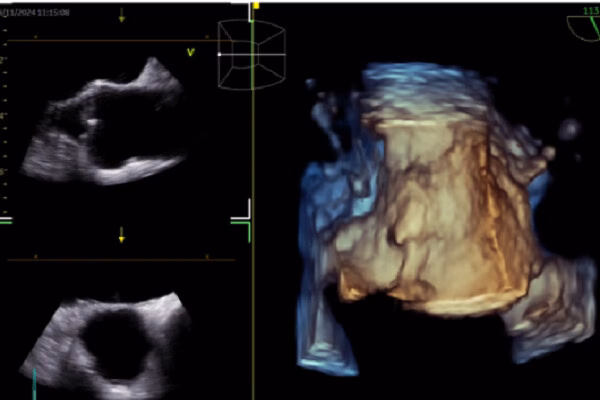

TS-BS Giang Minh Nhật chia sẻ về ứng dụng Trí tuệ nhân tạo (AI) trong tái định hình chăm sóc tim mạch tại hội nghị khoa học thường niên Bệnh viện Nhân dân Gia Định 2025. AI được ứng dụng rộng rãi trong hình ảnh học tim mạch giúp chẩn đoán và ra quyết định lâm sàng. Các ứng dụng này giúp nâng cao chất lượng hình ảnh.